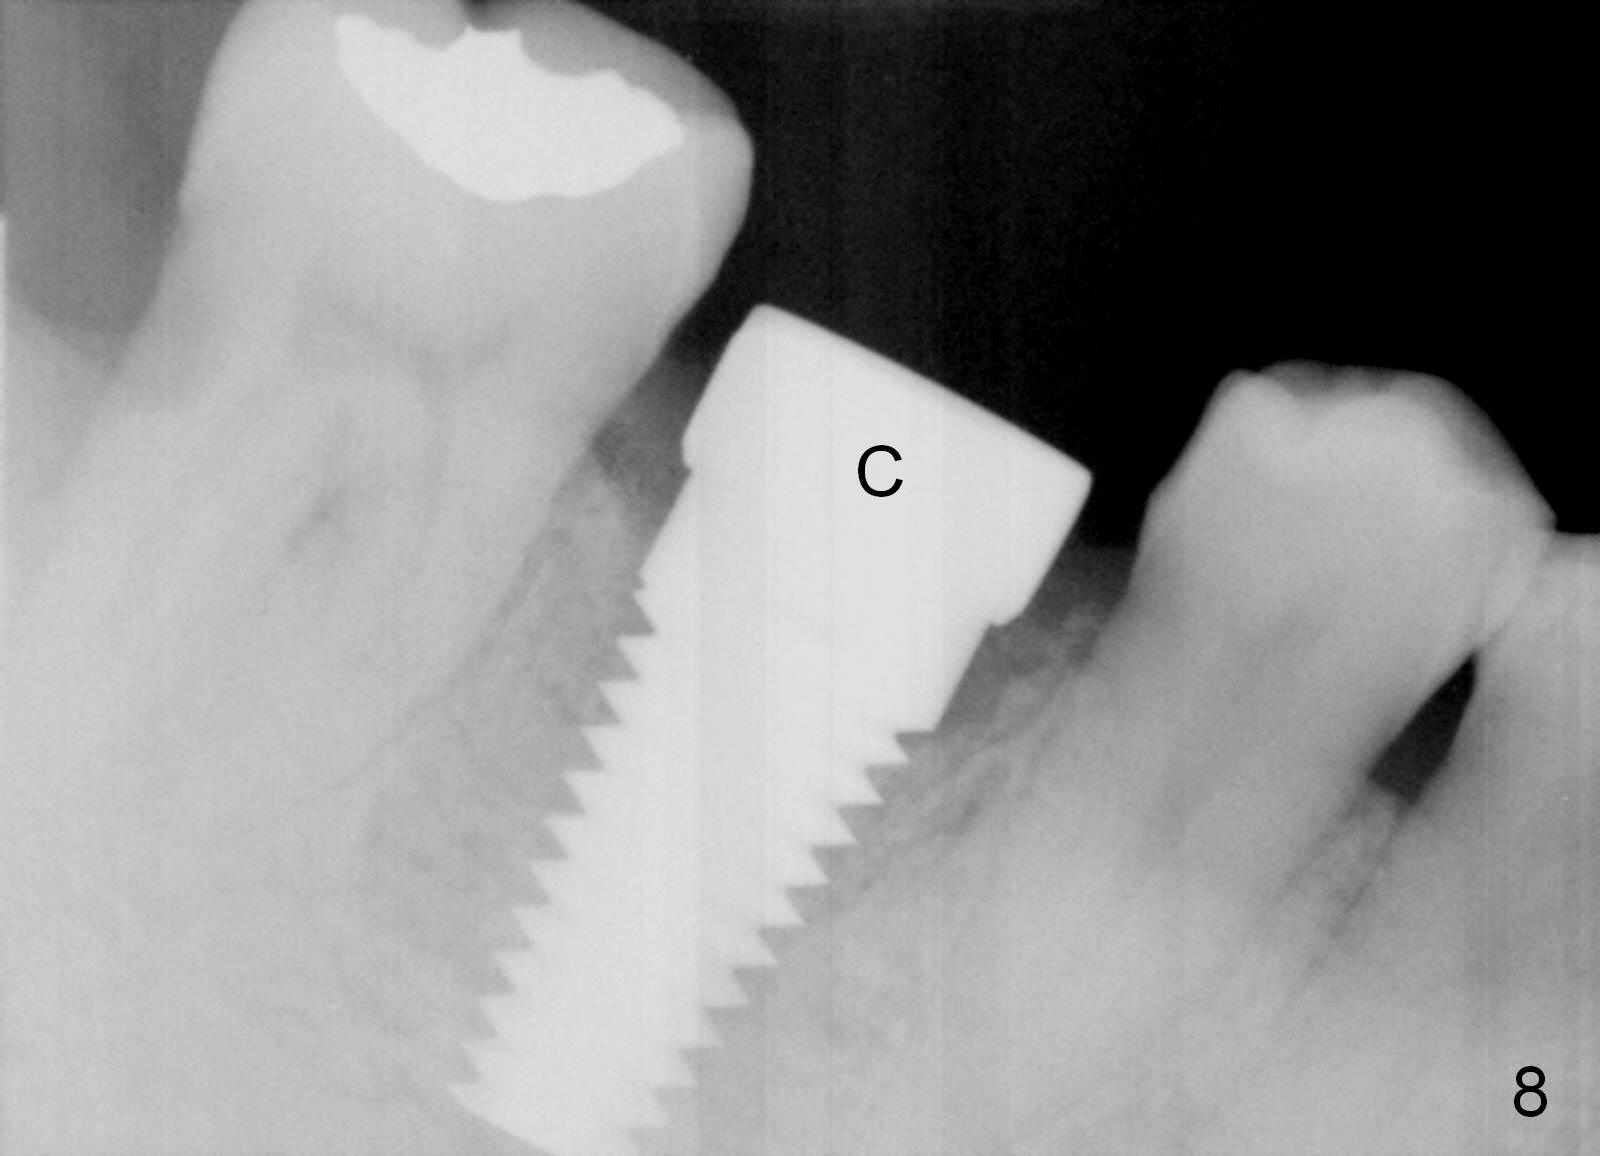

The patient returns for extraction and immediate implant after 7 days of oral Amoxicillin. There is a deep pocket mesiolingually in addition to the mesiobuccal fistula (Fig.1 <). The metal crown and then the tooth are sectioned. The crack of the mesial root is confirmed during extraction. The coronal portion of the mesiobuccal plate is defective, corresponding to the fistula. Both the mesial and distal sockets are large with a thin septum in between. Osteotomy is established at the base of the septum, slightly toward the mesial socket, as evidenced by a 5x20 mm tap in place (Fig.2). Finally, a 7x17 mm implant is placed (Fig.3 I; A: abutment; G: bone graft). The insertion torque is more than 60 Ncm.